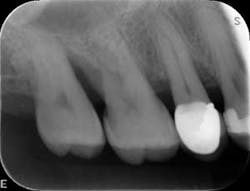

Dental examination revealed gingival swelling and bleeding on probing. Periodontal probing showed moderate-to-deep pocket depths in all posterior teeth (figures 1–3). Generalized bone loss was observed on radiographs (figures 4–6). Tooth vitality and percussion tests were negative. Teeth 2, 3, 31, 14, and 15 had Class III mobility. The patient was diagnosed with Type IV chronic adult periodontitis. Treatment options were discussed, and, after explanation, the patient agreed to the LANAP procedure.

Patient presentation before LANAP treatment (figures 1–6)